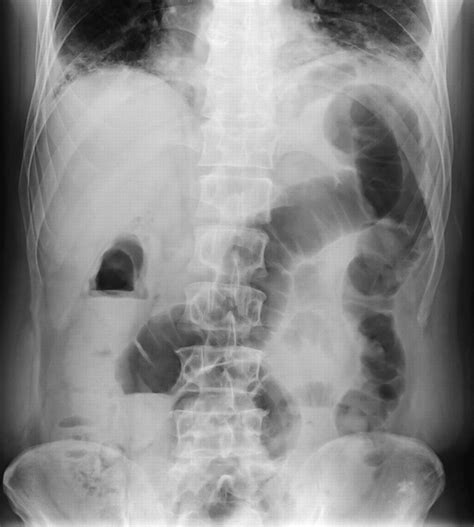

Interpreting Constipation in X-Ray

When interpreting an abdominal X-ray for constipation, radiologists look for several key indicators:

• Fecal Loading: The presence of a large amount of fecal matter in the colon.

• Colonic Dilatation: An enlarged colon, which may indicate chronic constipation.

• Air-Fluid Levels: The presence of air and fluid in the colon, which can suggest obstruction or slow transit.

These findings can help healthcare providers determine the severity of constipation and identify any underlying issues that may be contributing to the condition.